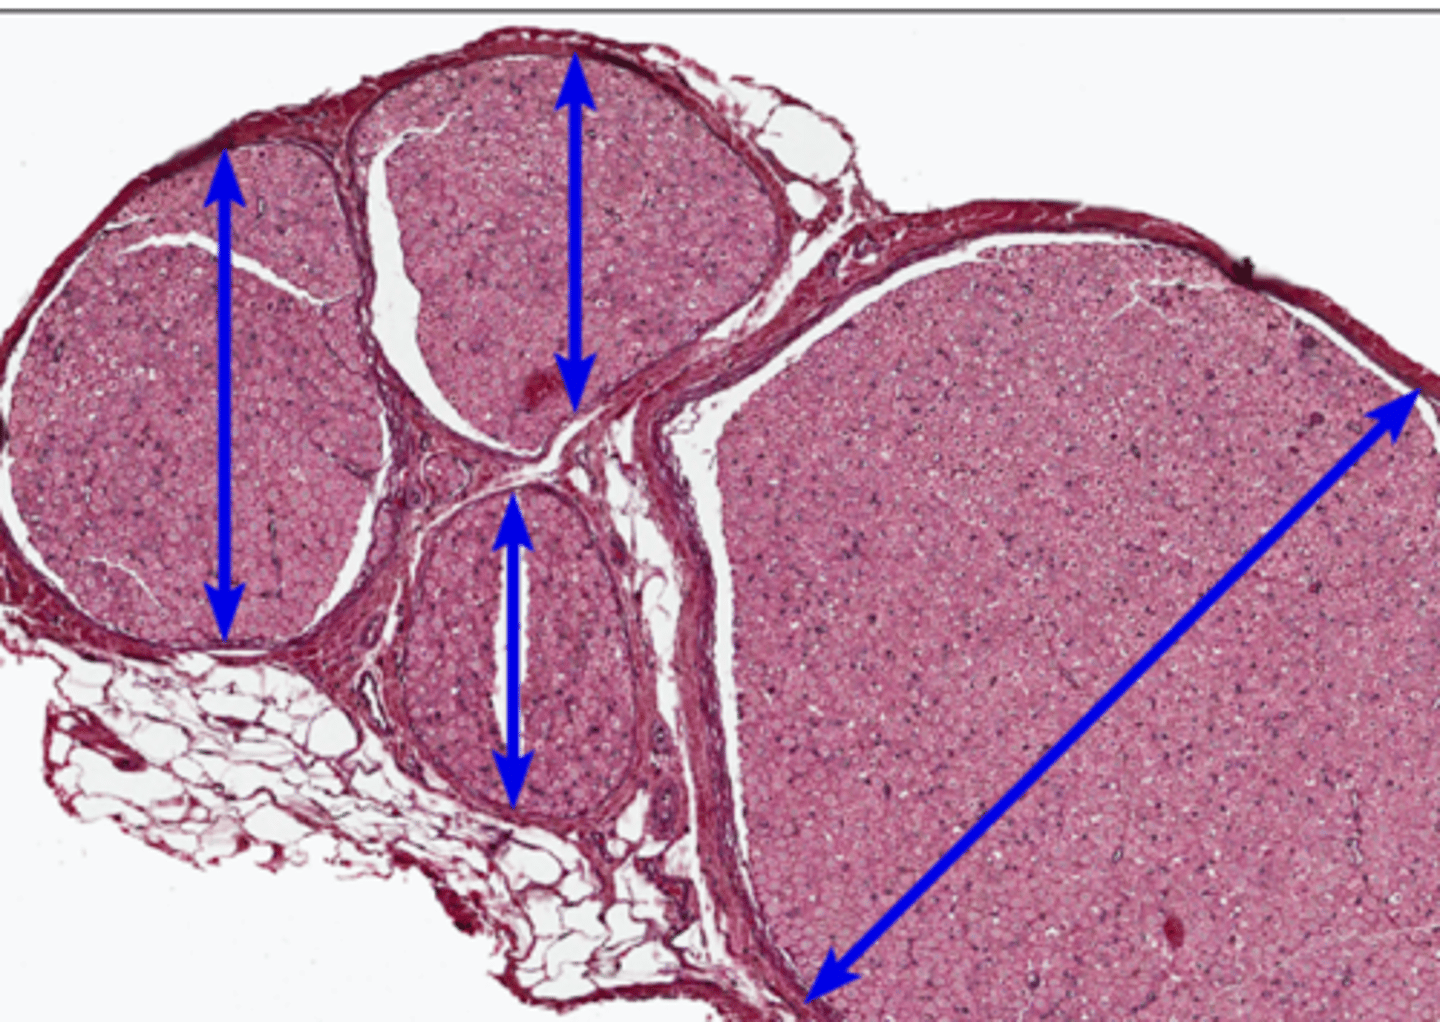

Epineurium

red arrow

fasicle

perineurium

blue arrow

Endoneurium

myelinated sheath

myelinated axon